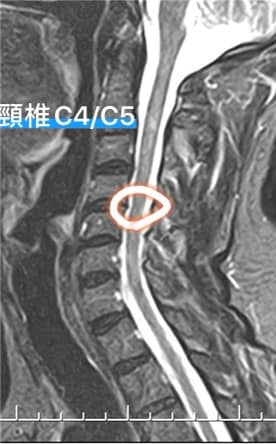

Cervical Spine Treatment Cases 頸椎治療案例 #疼痛三年頸椎病患者親手寫下治療紀錄 #交感神經型頸椎病 #症狀錯綜複雜 2020.10.02 #困擾四年多胸悶手麻頭暈醫案 #一切原因居然是頸椎出問題 #交感神經型頸椎病症狀錯綜... 2020.09.11 #交感神經型頸椎病引起的耳鳴 #耳鳴將近八個月終於得到重大改善 #曾經耳鳴到無法睡覺... 2020.08.22 #感謝板橋蘇先生熱情見證 #神經根型頸椎病卡壓 #曾痛痛到左手無法騎單車撥桿 #麻脹刺... 2020.08.04 #後縱韌帶鈣化引起椎管狹窄 #痛到完全無法睡覺長達半年以上 #原本已經準備開刀最後逆... 2020.07.16 #牽一頸而動全身的特殊醫案 #兩分鐘瞭解交感神經型頸椎病 #絕望的黑暗人生看到一絲希... 2020.07.03 #長達七年的頸椎疼痛是怎麼回事 #神經根型頸椎病 #低頭族跟家庭主婦辛苦了 #逆轉勝醫... 2020.07.01 #頸椎整合中醫微創療法 #感謝新竹黃大哥熱情見證 #逆轉勝成真醫案 2020.06.25 #頸椎病手術後也要要好好保健 #毛巾操很重要再度上場 #感謝某大醫學中心主任見證 2020.06.24 #這些症狀很可能都是頸椎出問題 #患者看七種不同科別醫師找不出原因 #交感神經型頸椎... 2020.06.09 #消失的頸椎曲線能夠回來嗎? #核磁共振前後對比椎管容積打開 #脊椎整合中醫微創療法❤... 2020.06.05 #感謝新竹薛大哥熱情見證 #頸椎整合中醫微創療法 治療:4/21~5/30(八次) 效果顯著... 2020.05.30 從宜蘭來的游小姐患者熱情見證 頸椎整合中醫微創療法 逆。轉。成。真。 2020.05.29 #脊髓型頸椎病案例 2020.05.26 #感謝新北市黃小姐熱情見證 #疼痛時間超過一年 #晨起麻痛到不行的日子長達半年以上 #... 2020.05.16 ← 上一頁 5 6 7 8 9 下一頁 →